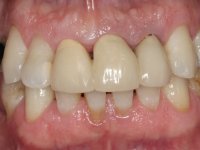

Patient male, 60 years old, non-smoker. After imaging and clinical examination, it was found that the patient had teeth 2.1 and 2.2 with extensive acrylic restorations, with screwed intra radicular posts and very poor endodontic treatments. Tooth 2.2 had an extensive apical lesion, the post had been placed on a false route and had mobility. Tooth 1.1 had an extensive resine restoration and tooth 1.2 presented a mesial restoration, also in composite resin, Class III type. The antero-superior sector was vestibularized, as consequence of a loss of vertical occlusion dimension associated with posterior edentulism. The patient showed reasonable periodontal health and satisfactory oral hygiene.

Endodontic treatments were performed and a metalic non screwed intra radicular post was placed on tooth 1.1. An alginate impression was made for laboratory confection of a reinforced acrylic provisional bridge, with teeth 1.1 and 2.2 as abutments and 2.2 as a pontic. After preparation of tooth 1.1 and root preparation of 2.1, the bridge was relined in mouth with self-polymerizable acrylic using a metal post for further retaining the prepared root canal on 2.1. Tooth 2.2 was cut at the gingival level to function as support. In the same session, the impression of the root canal of the 2.1 was made for the laboratory confection of a cast post and core. A double mixture technique with plastic tutor was used after previous canal vaseline with endodontic file and cotton. The provisional bridge was provisionally cemented and the cast post and core was made in the laboratory. Cast post and core cementation was made with resin-reinforced glass ionomer cement and the provisional bridge had to be readjusted to the new situation by removing the post at the site of 2.1. After careful surgical planning, a dental implant was placed, simultaneously with extraction of the root of tooth 2.2. The provisional bridge was placed by resting on the healing screw placed in the implant. The respected osteointegration period was 12 weeks, during which the provisional bridge was relined twice. After complete maturation of hard and soft tissues, definitive impressions were made. The gingival retraction technique was applied with an impregnated retraction cord and impression was performed using double mixture, open tray impression technique. A custom precious metal abutment implant was prepared in the lab, along with 3 metal caps to be used as infrastructures for the metal ceramic crowns. Particular care was taken in the confection of the cervical finishing line of the implant abutment, in order to follow the soft tissues emergence profile. Proof of infrastructures was done in the mouth being evaluated clinically and imagiologically. Collection of color information was done by the ceramist at the office. Ceramic was applied in the laboratory and the finished work was placed in the mouth after approval by the patient. Definitive cementation was made with resin-reinforced glass ionomer cement, and the first crown to be cemented was that of the implant, to facilitate removal of the excess.